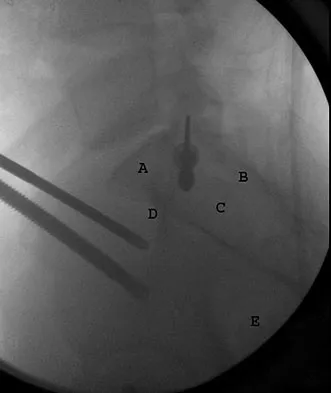

The injection shown in Figures 1a and 1b would most benefit a patient who reports which of the following symptoms?

Explanation